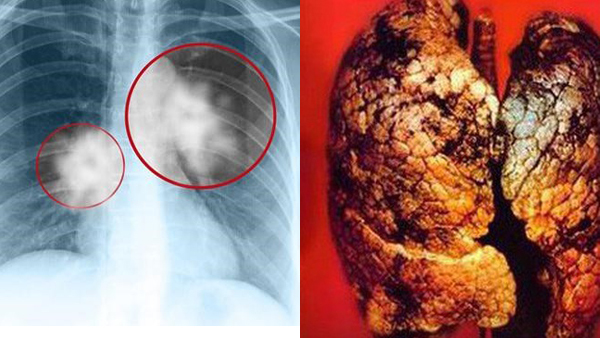

Ung thư phổi

Đây là căn bệnh ung thư phổ biến nhất ở nam giới và đứng thứ 3 ở nữ giới.Bệnh diễn biến nhanh, tỉ lệ tử vong lớn, trung bình mỗi phút có 3 người tử vong.